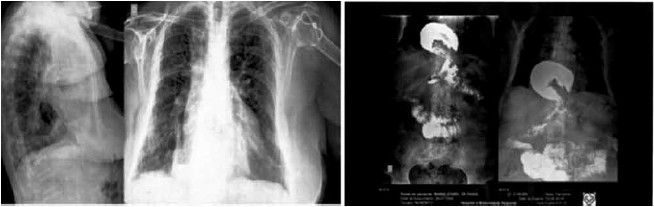

Mulher, 68 anos, com dispneia, fadiga, dor retroesternal, vômitos e refluxo gastroesofágico há dois anos, apresentou piora clínica com disfagia a líquidos, não tolerando decúbito para dormir nos últimos meses. Portadora de hipotireoidismo e hipertensão arterial controlados. Na investigação diagnóstica, foi realizada radiografia do tórax, que apresentou imagem retrocardíaca irregular. Posteriormente, prosseguiu-se a investigação com seriografia contrastada do esôfago-estômago-duodeno (imagens a seguir).

(Arquivo pessoal; imagens usadas com autorização)

De acordo com as informações do quadro clínico e os exames apresentados, o diagnóstico da paciente é: